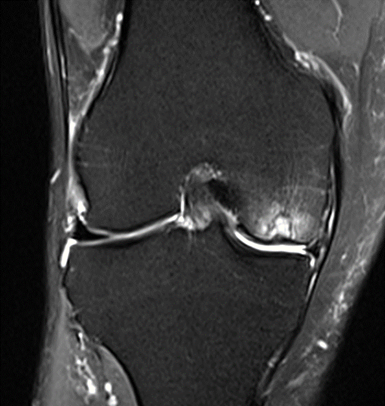

MRI scans illustrating the improvements regarding Group 2 are presented below, showing pre-treatment images with evident cartilage defects, pronounced bone marrow edema, and synovial inflammation, followed by post-treatment scans demonstrating improved joint structure, reduced edema, and decreased inflammation (Figures 12-29).

MRIs of Group 2

MRIs of Group 1

To provide a comparative perspective, additional MRI scans from Group 1 are shown subsequently. While patients in this group also displayed reductions in bone marrow edema, effusion, and synovitis, the improvements appeared less pronounced than those seen with the combined therapy. Pre-treatment MRI scans revealed extensive edema and synovial inflammation, which were partially reduced at the 2-month follow-up. However, residual joint effusion and subtle signs of inflammation remained present in some cases. These findings further support the potential benefit of combining the ChondroFiller® liquid with MSC therapy to achieve more comprehensive structural improvements and facilitate enhanced cartilage regeneration (Figures 30-41).